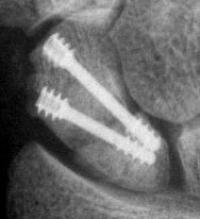

Case 8. Transscaphoid perilunate fracture dislocation...

Click for larger image

Two screws put in dorsally, LT ligament reinforced with a strip of extensor retinaculum left attached to the triquetrium and anchored into the lunate; temporary capitolunate pin.